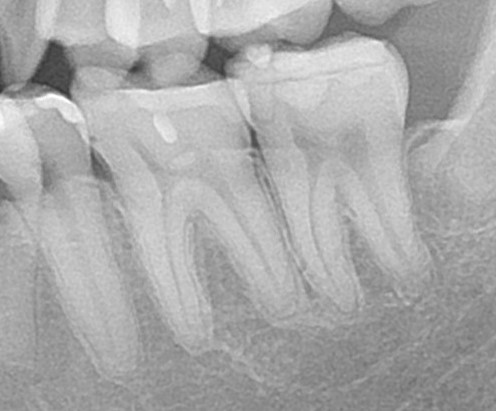

エックス線写真(レントゲン)で確認してみると、

歯とインレーの間に隙間や、ズレを認める。

担当医でやり直しはしてもらえず、当院で再治療を行う。

こちらは歯科医師の技術力による不具合。